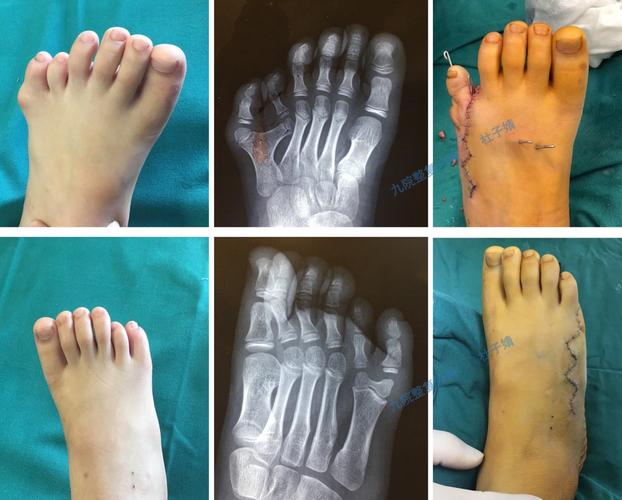

足背六边形皮瓣在第 4,5 趾并趾伴小趾多趾畸形矫形中的应用